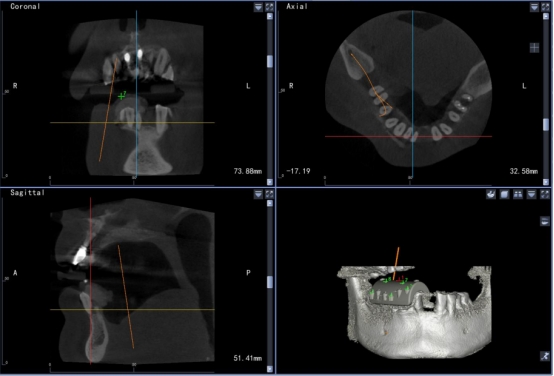

高精准度:采用国际领先的红外光学定位技术,准确为医生指引方向,准度可达到0.3mm,种植体植入方向、位置、角度、深度一目了然,确保了种植手术的可预期性,显著提高种植精度。

实时引导:全程监控手术工具与解剖结构的位置关系,轻松把控种植位点、角度和深度,实时引导术者按计划进行种植。

数字化动态导航系统犹如口腔中的GPS导航”,简单来说就是通过虚拟数字化软件设计,提前设计好修复体三维位置,结合精准的红外光学定位技术,在种植手术过程中,实现全程实时的导航。使使种植医生实时监控和调整手术的进程。